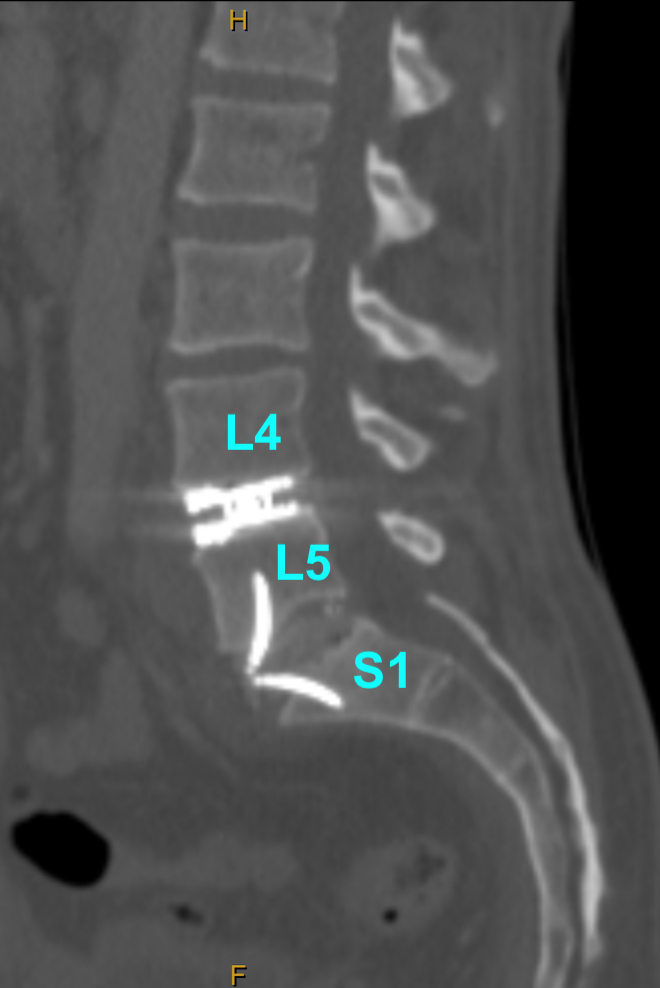

Image 2A (above). This business owner, an active and athletic chap, wore out his lower lumbar discs, and was quite limited by that.

Image 2B (above). The solution for him was a L4-5 artificial disc (total disc arthroplasty/TDA aka total disc replacement/TDR) and a L5-S1 sleek fusion cage. This is also known as a “hybrid” reconstruction. A lovely restoration of disc heights and lumbar lordosis, and indirect neural decompression. Find out more about these prosthetics by CLICKING HERE.